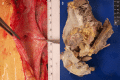

BACKGROUND Percutaneous catheter radiofrequency ablation (RFA) and cryoablation of the left atrium and pulmonary vein ostia have become successful therapeutic modalities in the management of atrial fibrillation. Atrio-esophageal fistula is a rare complication. Awareness of complication risk is imperative because without prompt diagnosis and urgent surgical intervention, the outcome is often fatal. We present 3 cases of atrio-esophageal fistula following percutaneous catheter radiofrequency ablation (RFA). CASE REPORT Case 1: A 72-year old white male presented 27 days after percutaneous RFA for atrial fibrillation with fever, altered mental status, and melena. Esophagogastroduodenoscopy (EGD) revealed a 1-cm defect in the mid-esophagus. Upon thoracotomy, severe hemorrhage ensued from a concomitant injury to the left atrium. Multiple attempts to repair the left atrial perforation were unsuccessful and the patient died. Case 2: A 71-year old white male presented 29 days after percutaneous RFA for atrial fibrillation with fever and tonic-clonic seizure. Recognition of possible atrio-esophageal fistula was considered and confirmed on thoracotomy. Surgical fixation of the left atria and esophagus were performed. The patient survived and was discharged to a skilled care facility. Case 3: A 75-year old white male presented 24 days after percutaneous RFA for atrial fibrillation with chest pain. An echocardiogram revealed a large pericardial effusion and pericardiocentesis was performed. Despite aggressive measures, the patient died. The autopsy demonstrated a communicating esophageal fistula with the right pulmonary vein. CONCLUSIONS Clinicians tending to patients who have recently undergone atrial ablation need to be aware of atrio-esophageal fistula as a rare but highly fatal complication.